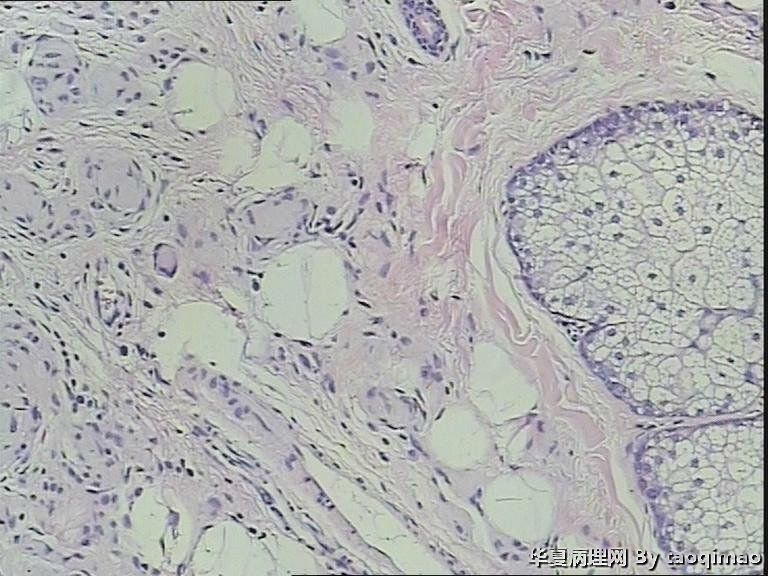

两例头皮肿物有差别么

岁女,头皮肿物,带皮组织一块

1x1

,皮瓣上可见一灰白结节大小

0.6x0.6

,皮瓣大小

1x0.4

,

面灰白质软。

门诊患者这一例没有其它更多信息

第一:皮内痣 第二:皮内痣并表皮囊肿